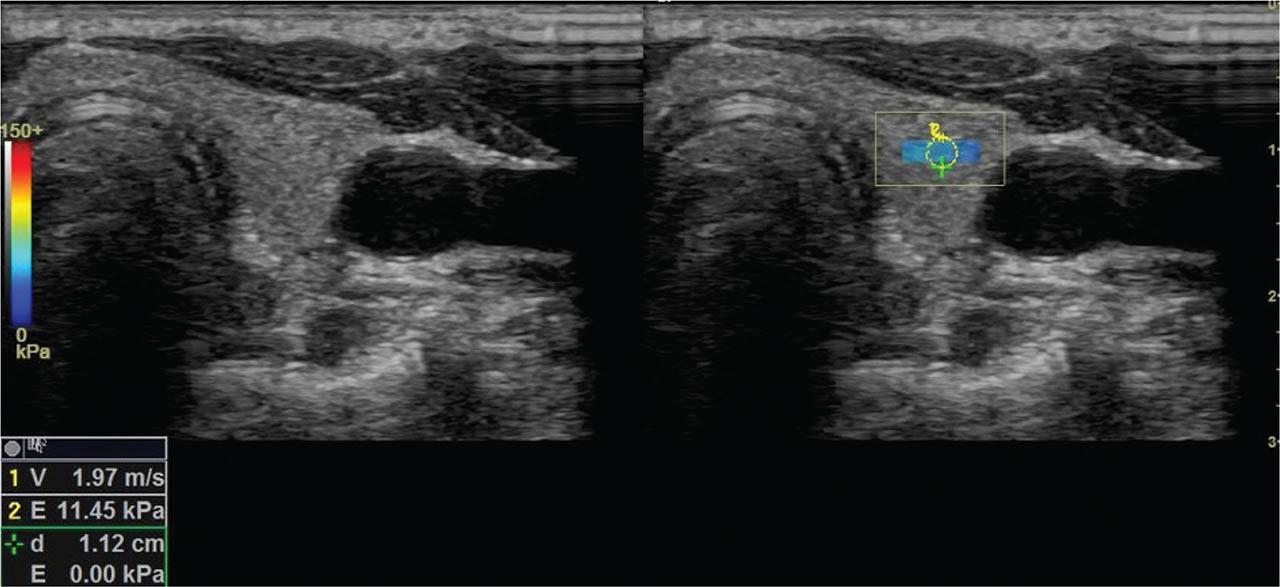

Figure 2

Shear wave velocity measurement in a patient with SCA. Parenchymal stiffness measured in the ROI on the left lobe was 11.45 kPa. ROI, region of interest; SCA, sickle cell anemia.